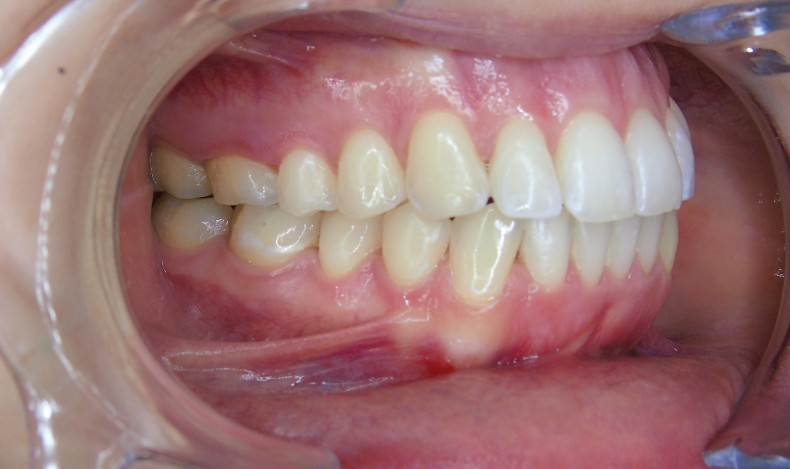

Der extraorale Befund (Abb. 1a–c) ergab ein gerades Durchschnittsgesicht mit leicht vergrößertem Nasolabialwinkel, ein symmetrisches Gesicht bei potenziell inkompetentem Lippenschluss sowie einen dolichofazialen Gesichtstyp. Intraoral lag beidseits annähernd eine Angle-Klasse I mit frontal offenem Biss (–2,5 mm) sowie ein dental-transversal zu schmaler Oberkiefer vor, woraus ein Kopfbiss von 13 und 23 resultierte. Des Weiteren zeigten sich ein persistierendes viszerales Schluckmuster und eine Inkongruenz der Kiefermitten (Abb. 2a–e; Abb. 3).

Durch sogenannte Optimized-Extrusion-Attachments wurde eine Extrusion der oberen Frontzähne von max. 2,3 mm und der unteren Frontzähne von max. 1,4 mm geplant (Abb. 4a–c). Mithilfe einer leichten Expansion der Prämolarenregion konnte der Platzmangel im Oberkiefer ohne ASR kompensiert werden.

Sechs Monate nach Abschluss der Therapie besteht weiterhin ein stabiles Ergebnis. Wie im Vergleichsbild (Abb. 5a–c) zu sehen ist, konnte die geplante vertikale Korrektur vollständig erzielt und die Mittellinie bis auf eine MLV von 1 mm nach rechts im UK korrigiert werden.

Somit kann gezeigt werden, dass auch ohne operativen Eingriff oder festsitzende Apparaturen in kürzester Zeit ein ästhetisch und funktionell zufriedenstellendes Ergebnis erzielt werden kann (Abb. 6a–c; Abb. 7a–e). Es wird daher nachvollziehbar dargestellt, dass bei entsprechender Indikation Aligner für die Behandlung frontal offener Bisse eine hervorragende Alternative zu den konventionellen Behandlungsmethoden sein können. Voraussetzung für diesen Therapieansatz ist ein motivierter Patient mit guter Compliance.